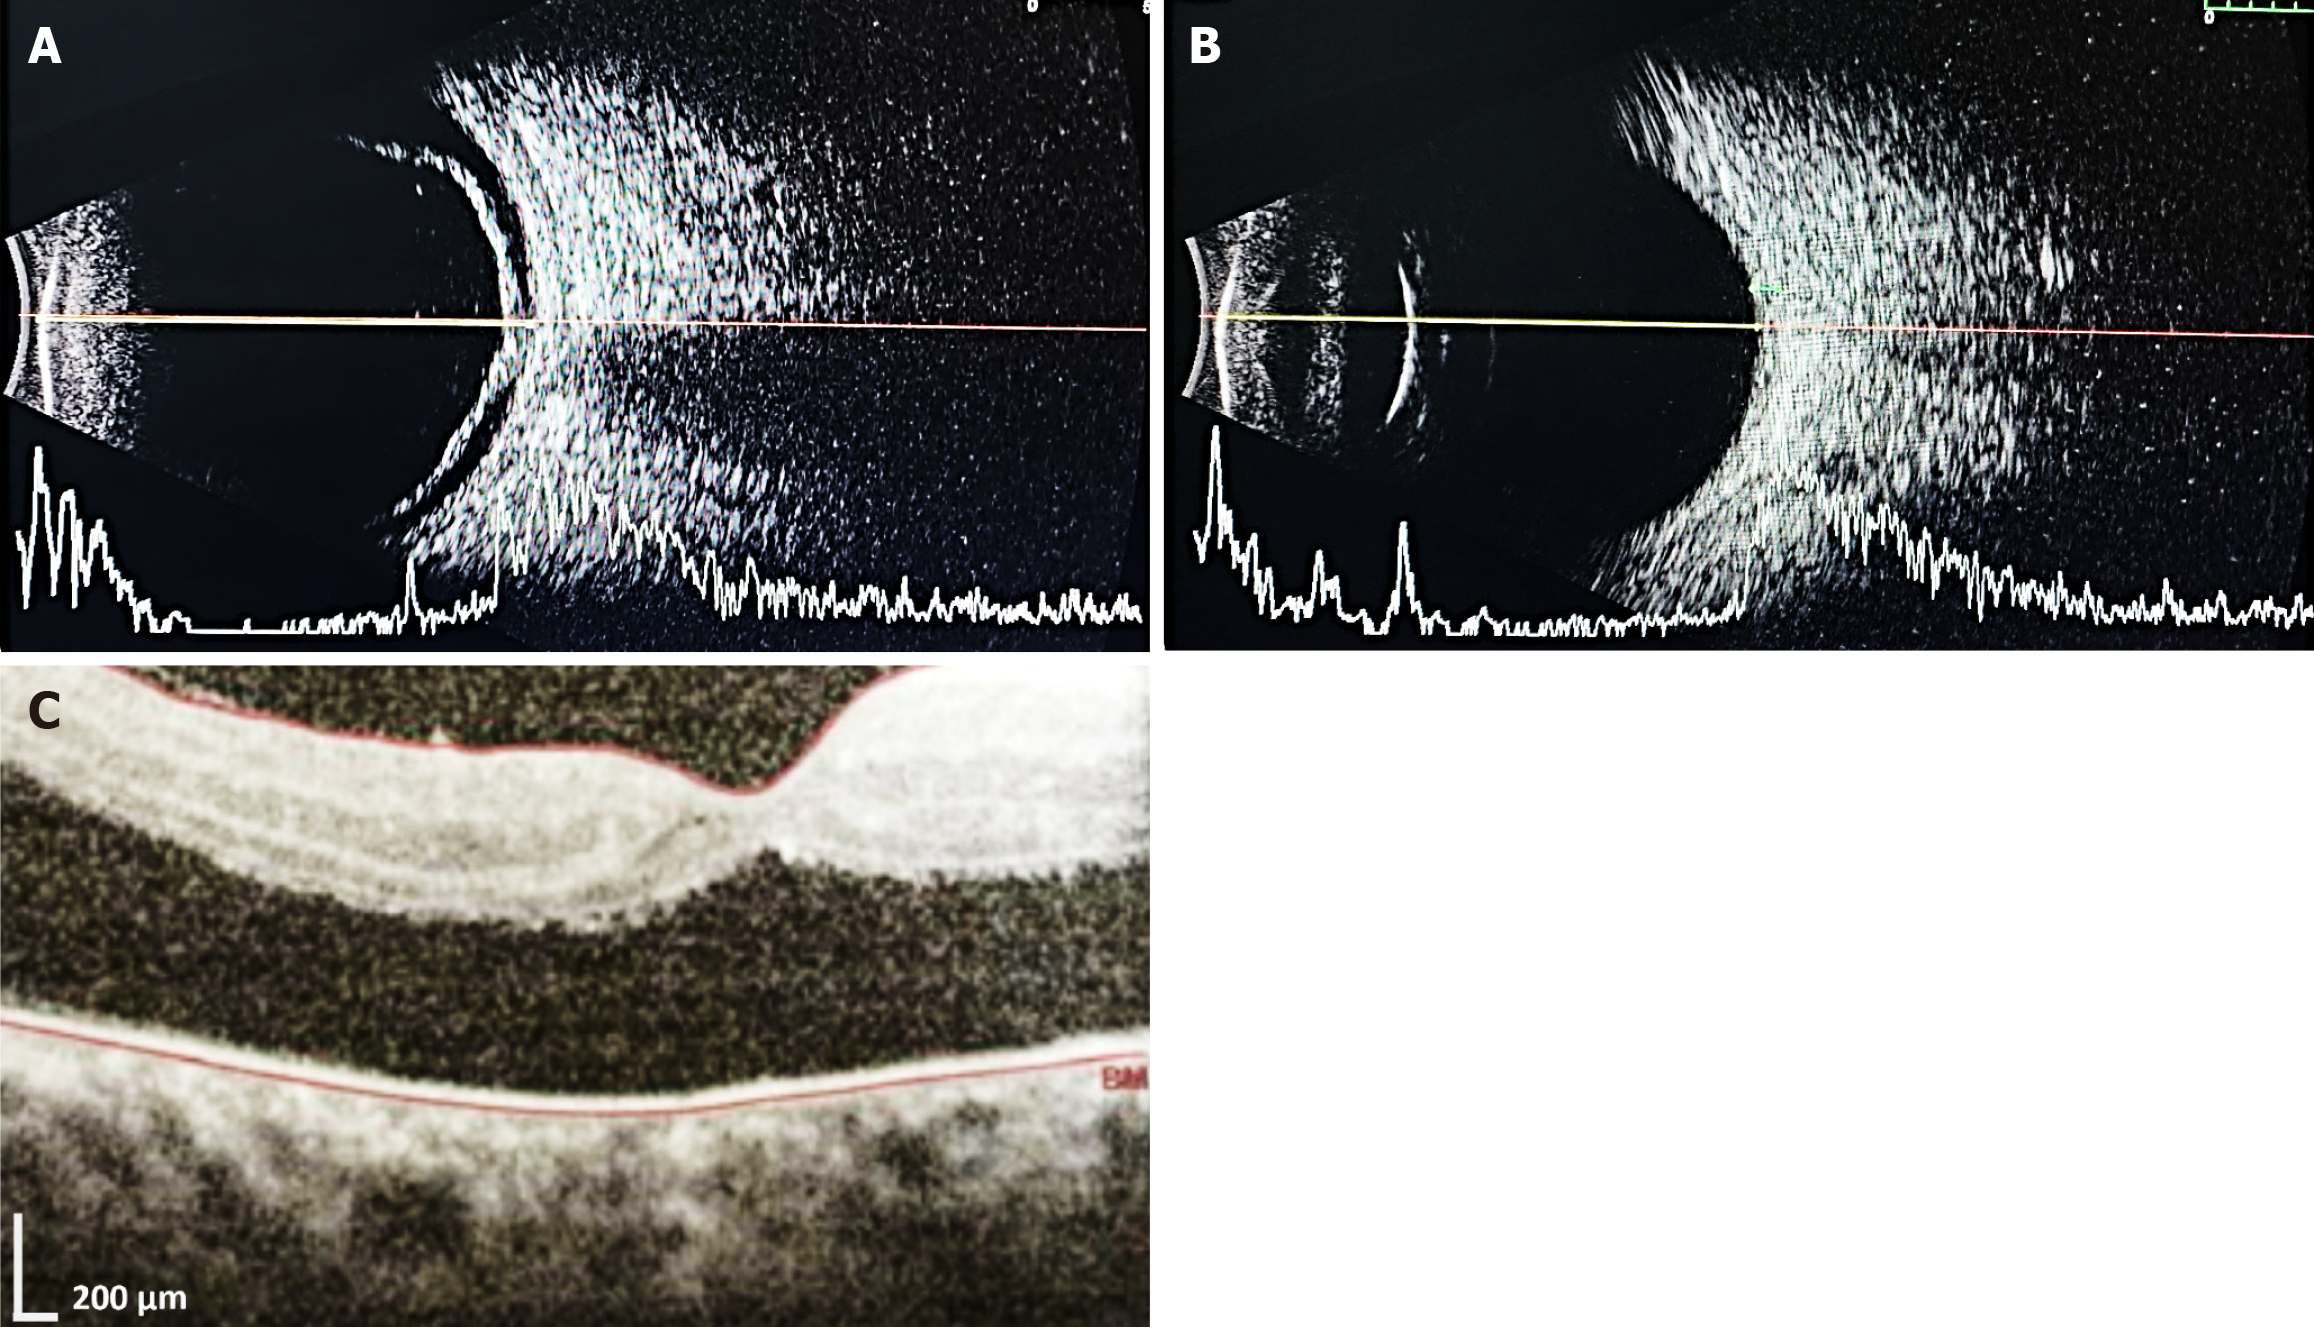

Case 1: B-scan ultrasonography OU revealed bilateral vitritis with no evidence of retinal or choroidal detachment. Axial length was 22.14 mm in both eyes. The retina-choroid-sclera complex was within normal limits.

Case 2: B-scan ultrasonography OU revealed an anechoic vitreous cavity with no retinal or choroidal detachment. Axial length was 23.13 mm OD and 23.74 mm OS. The retina-choroid-sclera complex appeared thick, measuring 1.24 mm in OD and 1.16 mm in OS. Parents of both patients refused ultrasonography of the joints citing financial constraints.

The patient was readmitted after 5 months for oral mucosal ulcers and received an injection of methotrexate 9 mg stat (10 mg/m²) with leucovorin rescue. Three doses of adalimumab (20 mg/0.4 mL) were administered subcutaneously at monthly intervals over the next 3 months. Fundus examination OD during this period revealed media haze with fibrovascular proliferation over the disc secondary to retinal vasculitis and exudative shallow retinal detachment (sparing the superior quadrant), which was confirmed by ultrasonography B-scan examination and optical coherence tomography (Figure 4). B-scan OS revealed an anechoic vitreous cavity, an intact retina-choroid-sclera complex, and a normal optic nerve head. Topical prednisolone and homatropine eye drops were restarted in OD, after which the clinical condition gradually improved. Two months later, the child suddenly developed painful bilateral foot ulcers on the lateral aspects of the soles, which were initially small (approximately 1 cm) but later became matted and enlarged (Figure 5) with ass